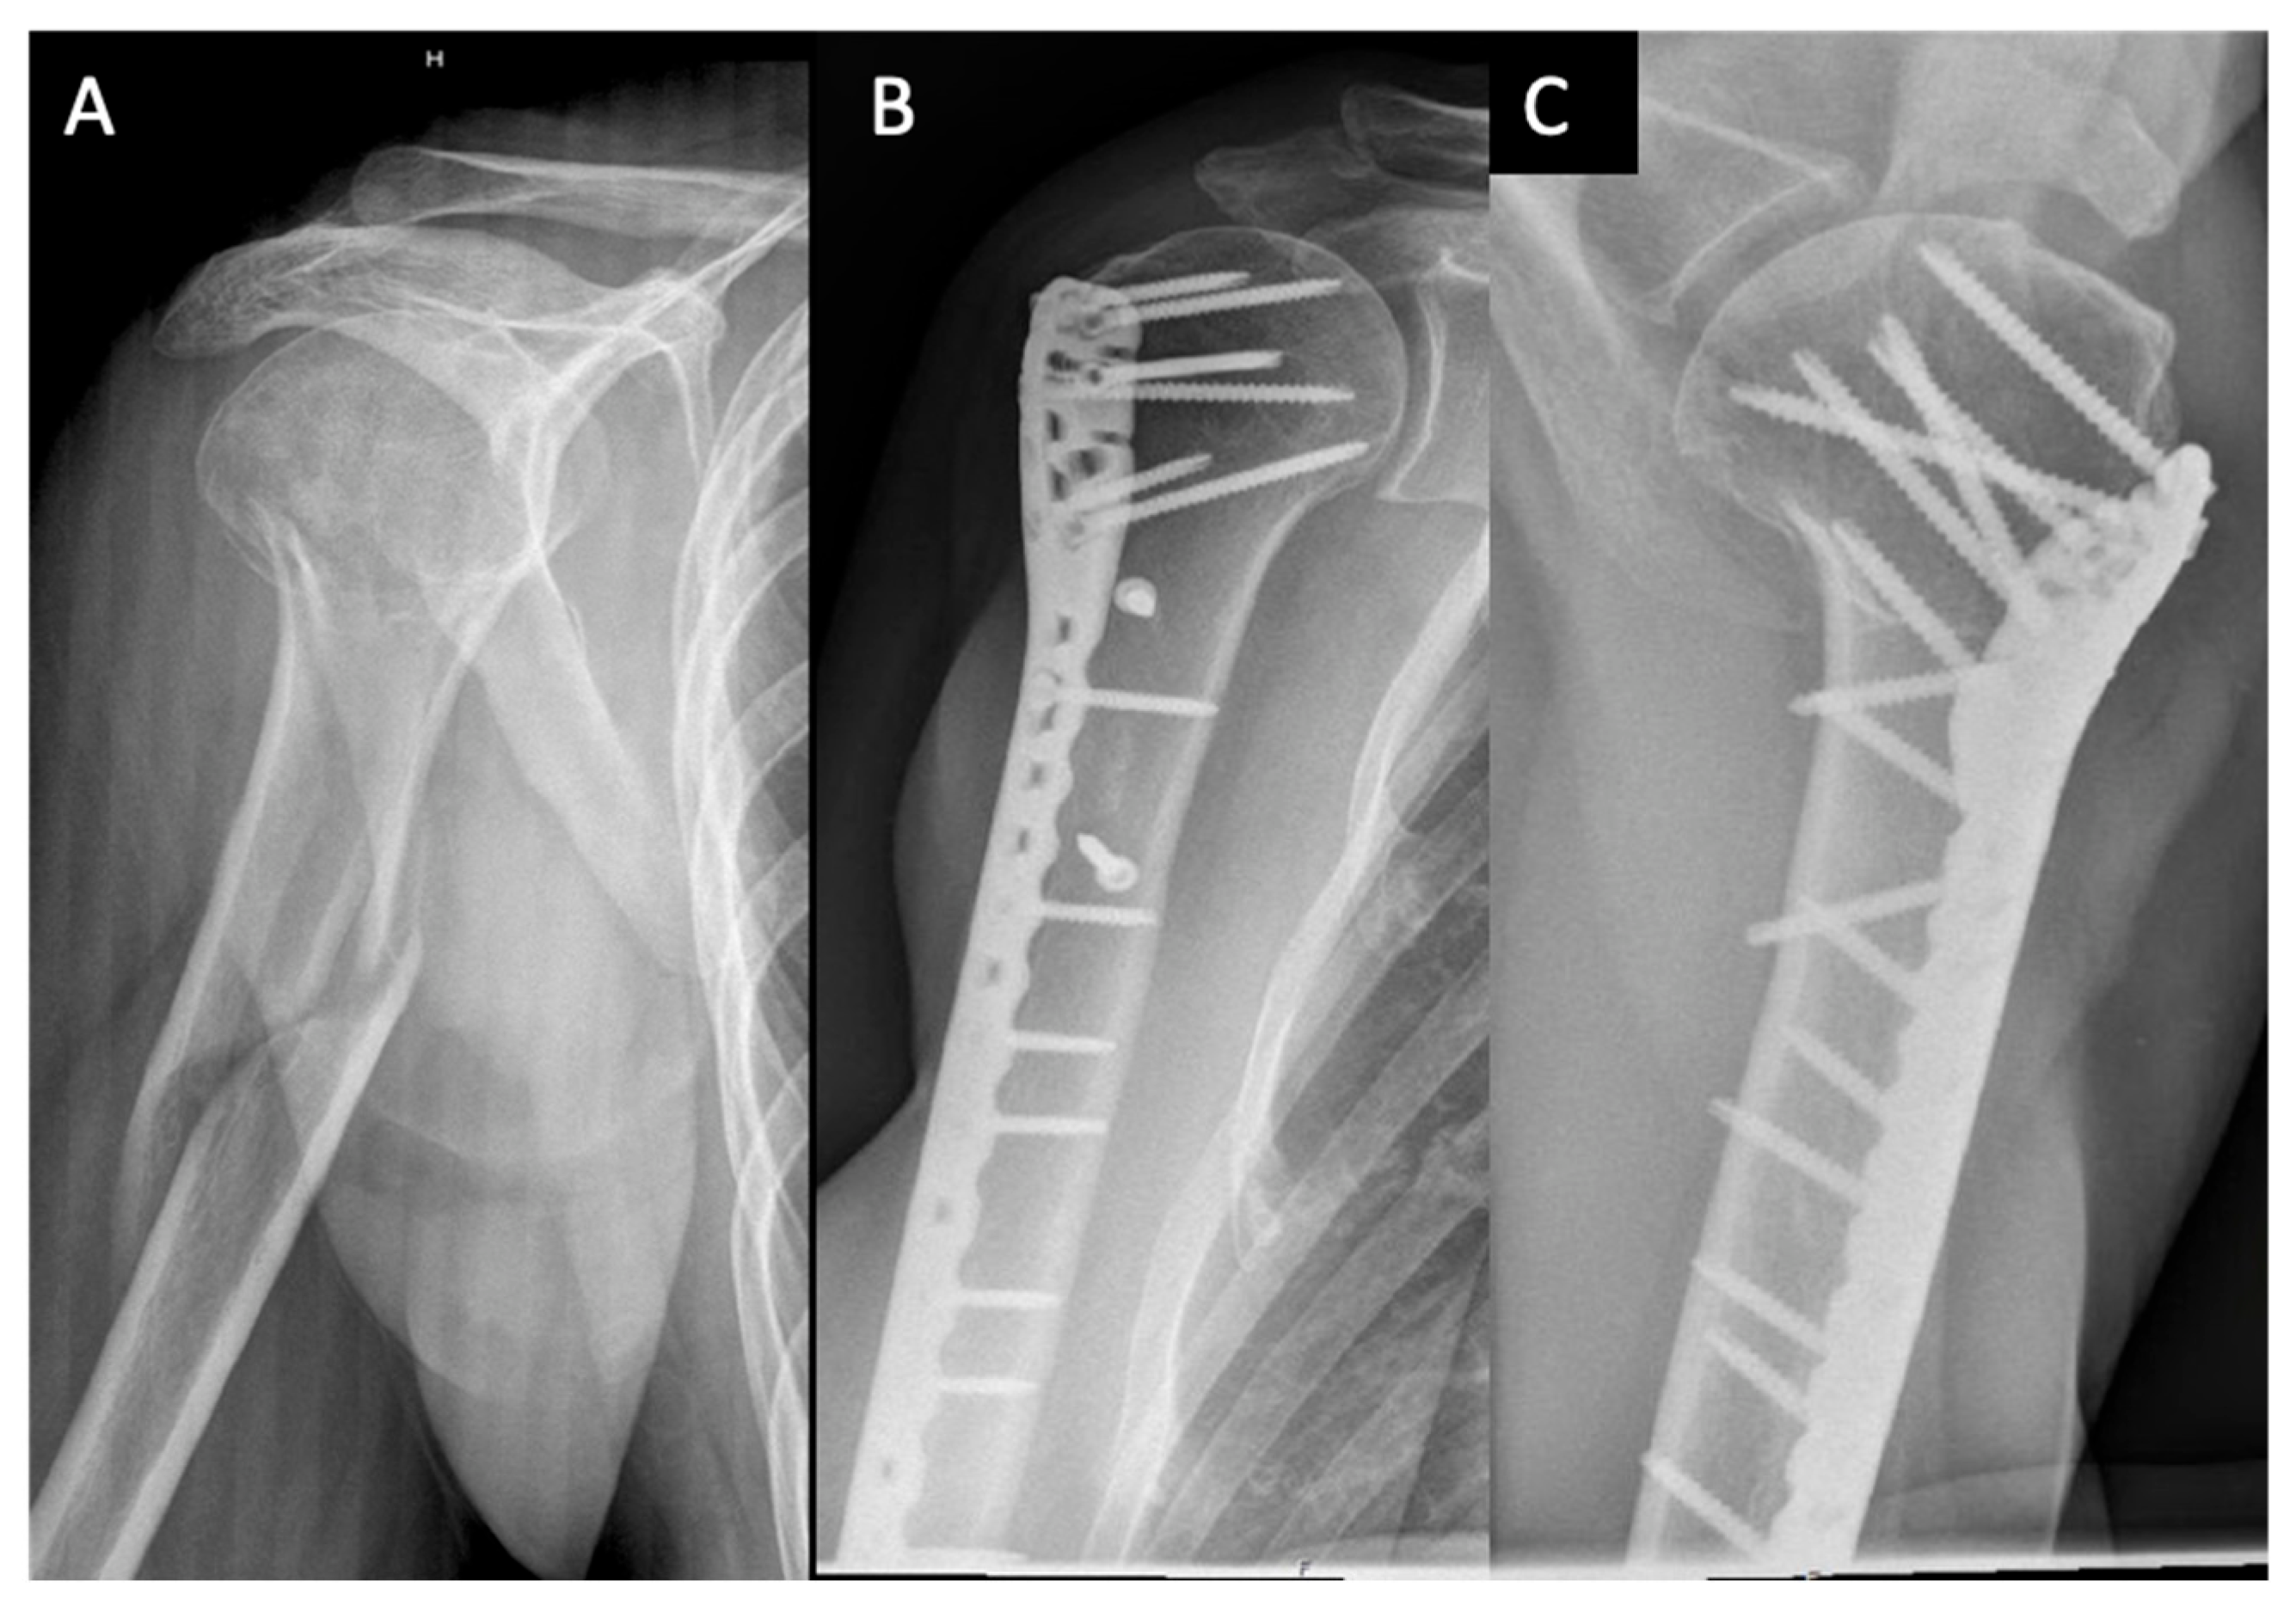

2. Materials and Methods

3. Results